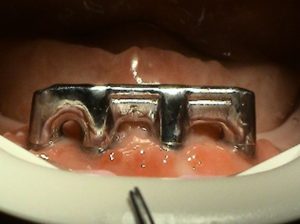

2. PHASE – state before making immediate impressions

3. PHASE – prosthetic fabrication of temporary crown on implant